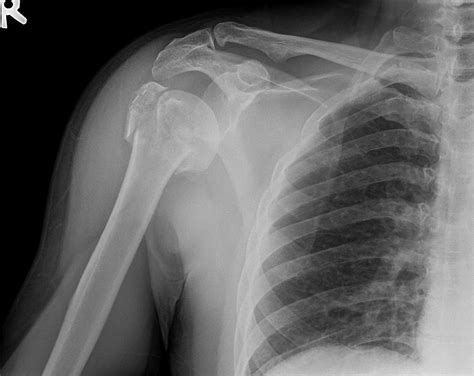

A proximal humerus fracture occurs at the top of the humerus, the long bone in the upper arm. This type of fracture is often the result of a fall onto an outstretched hand or a direct blow to the shoulder. The proximal humerus is composed of several parts, including the head, greater tuberosity, lesser tuberosity, and the surgical neck. Fractures can occur in any of these areas, and the severity can vary from minor cracks to complete breaks.

Diagnosing Proximal Humerus Fractures

Diagnosing a proximal humerus fracture involves a combination of physical examination and imaging tests. The diagnostic process typically includes:

• Imaging Tests: X-rays are the primary imaging tool used to diagnose proximal humerus fractures. In some cases, additional tests such as CT scans or MRIs may be ordered to provide more detailed images.